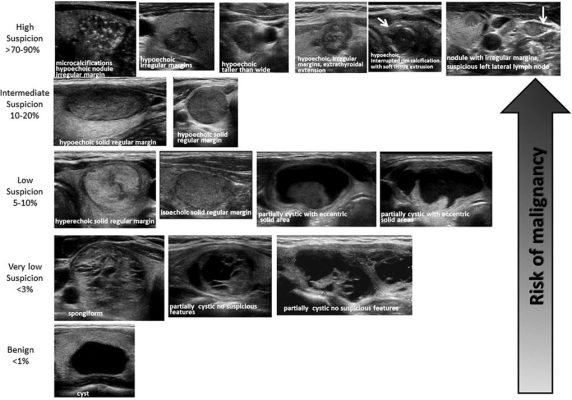

– Siêu âm tuyến giáp là thăm dò hữu ích trong đánh giá tuyến giáp, giúp đánh giá hình thái và độ lớn tuyến giáp. Có khoảng 30-50% người bệnh bướu giáp nhân, sờ tuyến giáp bình thường được siêu âm giáp phát hiện. Siêu âm cho biết số lượng, hình dạng nhân, đồng thời giúp hướng dẫn chọc hút bằng kim nhỏ để chẩn đoán tế bào học. Siêu âm giúp theo dõi sau điều trị.

Hình ảnh: đặc tính nhân giáp dưới siêu âm và nguy cơ ung thư